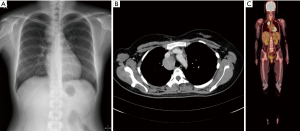

Chest X-ray and chest computed tomography (CT) confirmed a mass (6 cm × 4 cm × 4 cm) at the right superior and mid-mediastinum (Figure 1A,B). Positron emission tomography (PET) showed accumulation of fluorine-18-2-fluoro-2-deoxy-D-glucose in the tumor at a maximum standard uptake value of 9.21, whereas no other abnormal uptake suggestive of a metastatic lesion was found (Figure 1C). On the basis of the imaging findings, preoperative differential diagnoses included lymphoma, CD, thymoma, and neurogenic tumor. Diagnostic thoracoscopic surgery was planned based on the suspicion of lymphoma. A double-lumen endotracheal tube was placed, and the patient was positioned in the left lateral decubitus position. With single-lung ventilation, an initial 10-mm port was placed in the seventh intercostal space at the midaxillary line. This was followed by placement of two additional 10-mm ports in the fifth intercostal space at the anterior axillary line and the sixth intercostal space at the posterior axillary line.